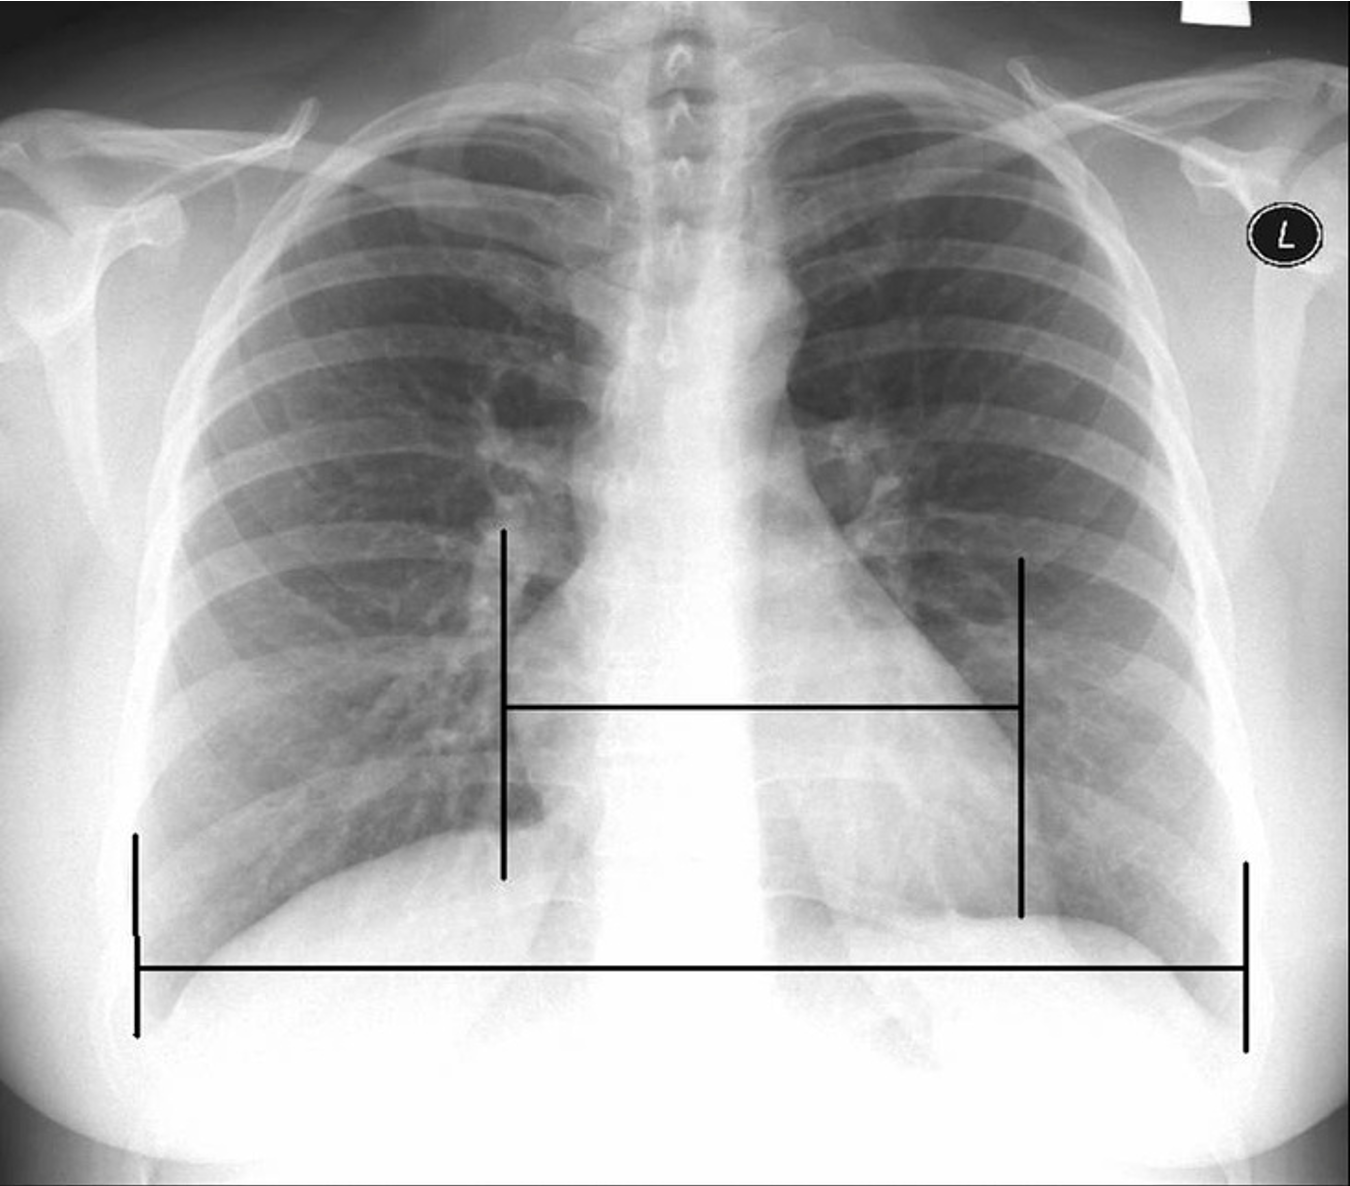

A cardiothoracic ratio above __ may indicate cardiomegaly.

0.5

The width of the heart should not be less than ___ the width of the thoracic cavity.

½